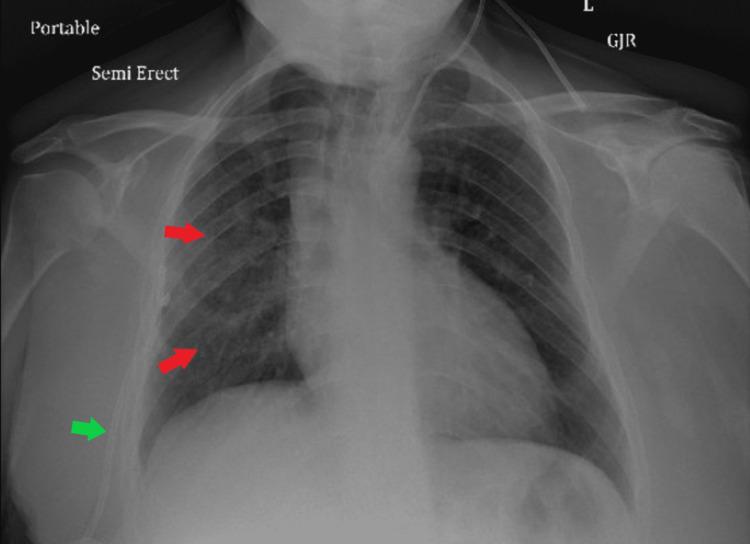

Antineutrophil cytoplasmic antibody (ANCA)-associated vasculitis is an autoimmune inflammatory disease that usually affects the small-sized vasculature, most notably of the lungs and kidneys. One of the challenges of suspecting and diagnosing the condition lies in the insidious and unclear symptoms of presentation. In this case report, we discuss the case of a patient who initially presented with solely unclear pulmonary symptoms, without other organ system dysfunction.

抗中性粒细胞胞浆抗体(ANCA)相关性血管炎是一种自身免疫性炎症性疾病,通常累及小血管,最显著的是肺部和肾脏的血管。怀疑和诊断该病的挑战之一在于其症状隐匿且不明确。在本病例报告中,我们讨论了一名患者的病例,该患者最初仅表现为不明确的肺部症状,而无其他器官系统功能障碍。